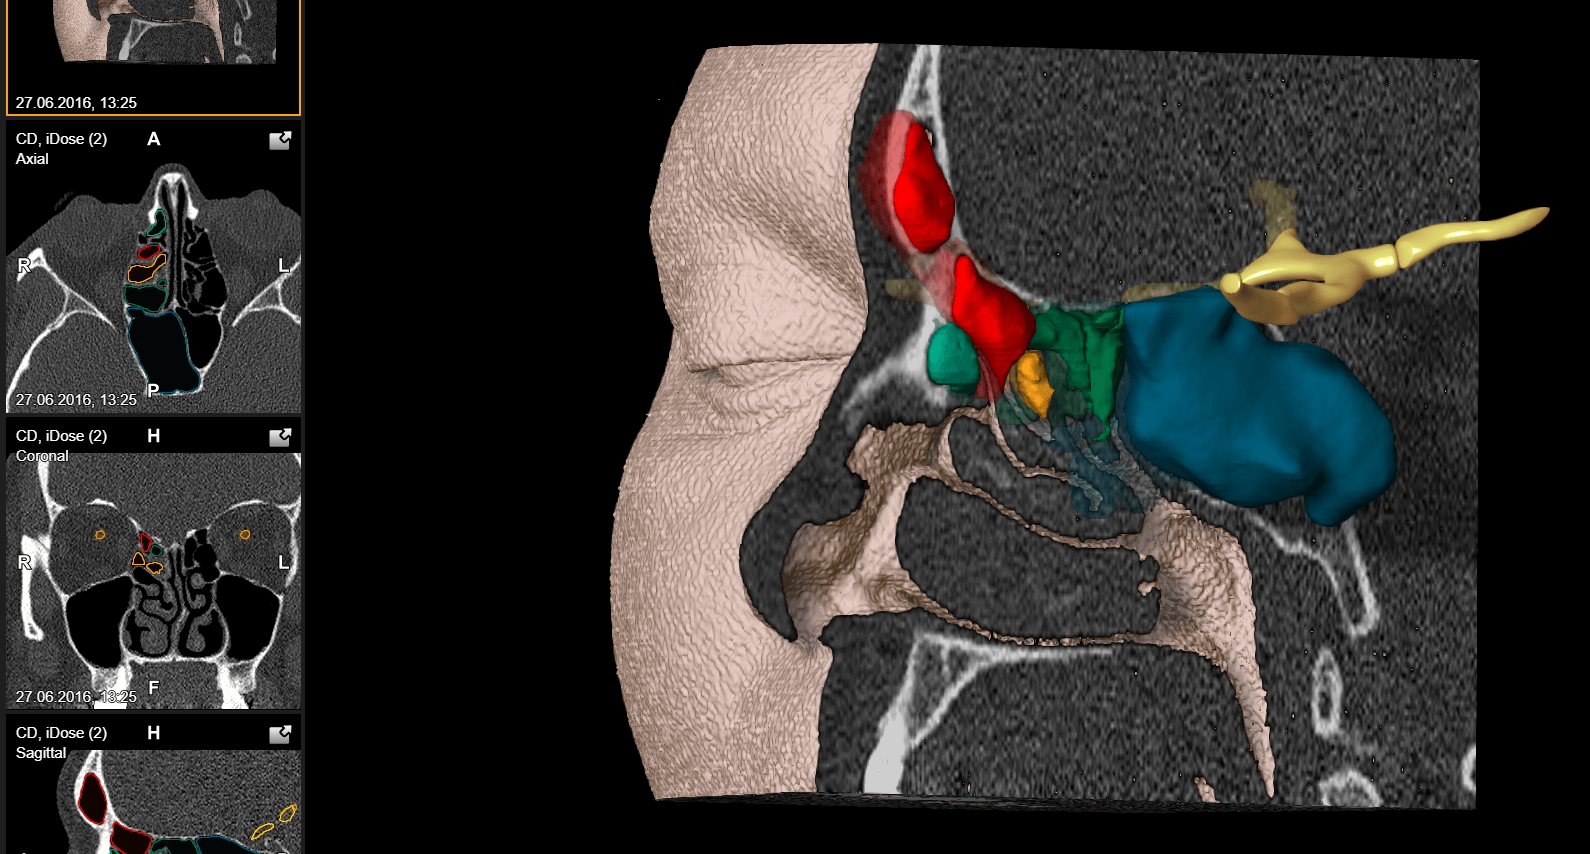

For their methods, they used a head phantom constructed with soft tissue structures of the face. A 3D dataset of the phantom was then created and an optimal trajectory to the foramen ovale was generated using a stereotactic planning station. This plan was transferred to the AR headset to be used for AR-guided cannulation, which involved superimposing the imaging data and aligning it with the phantom.

Watch the video under Methods to see how AR aided in planning